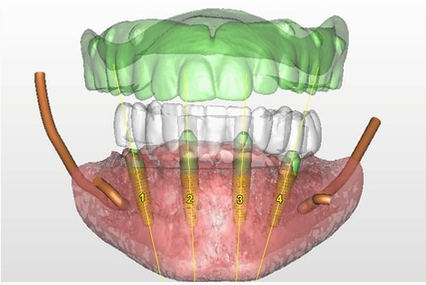

- In Implantology, the dentist can see vital anatomical structures, nerves, sinuses and the roots adjacent to the implants;

Implantology: Used for; better images of the bone status, the location of the mandibular nerve, sinus health, etc.

3D imaging is particularly useful in dental implantology, transmitting accurate information about bone structure, as well as important anatomical structures, allowing for better diagnosis and successful surgical procedures.